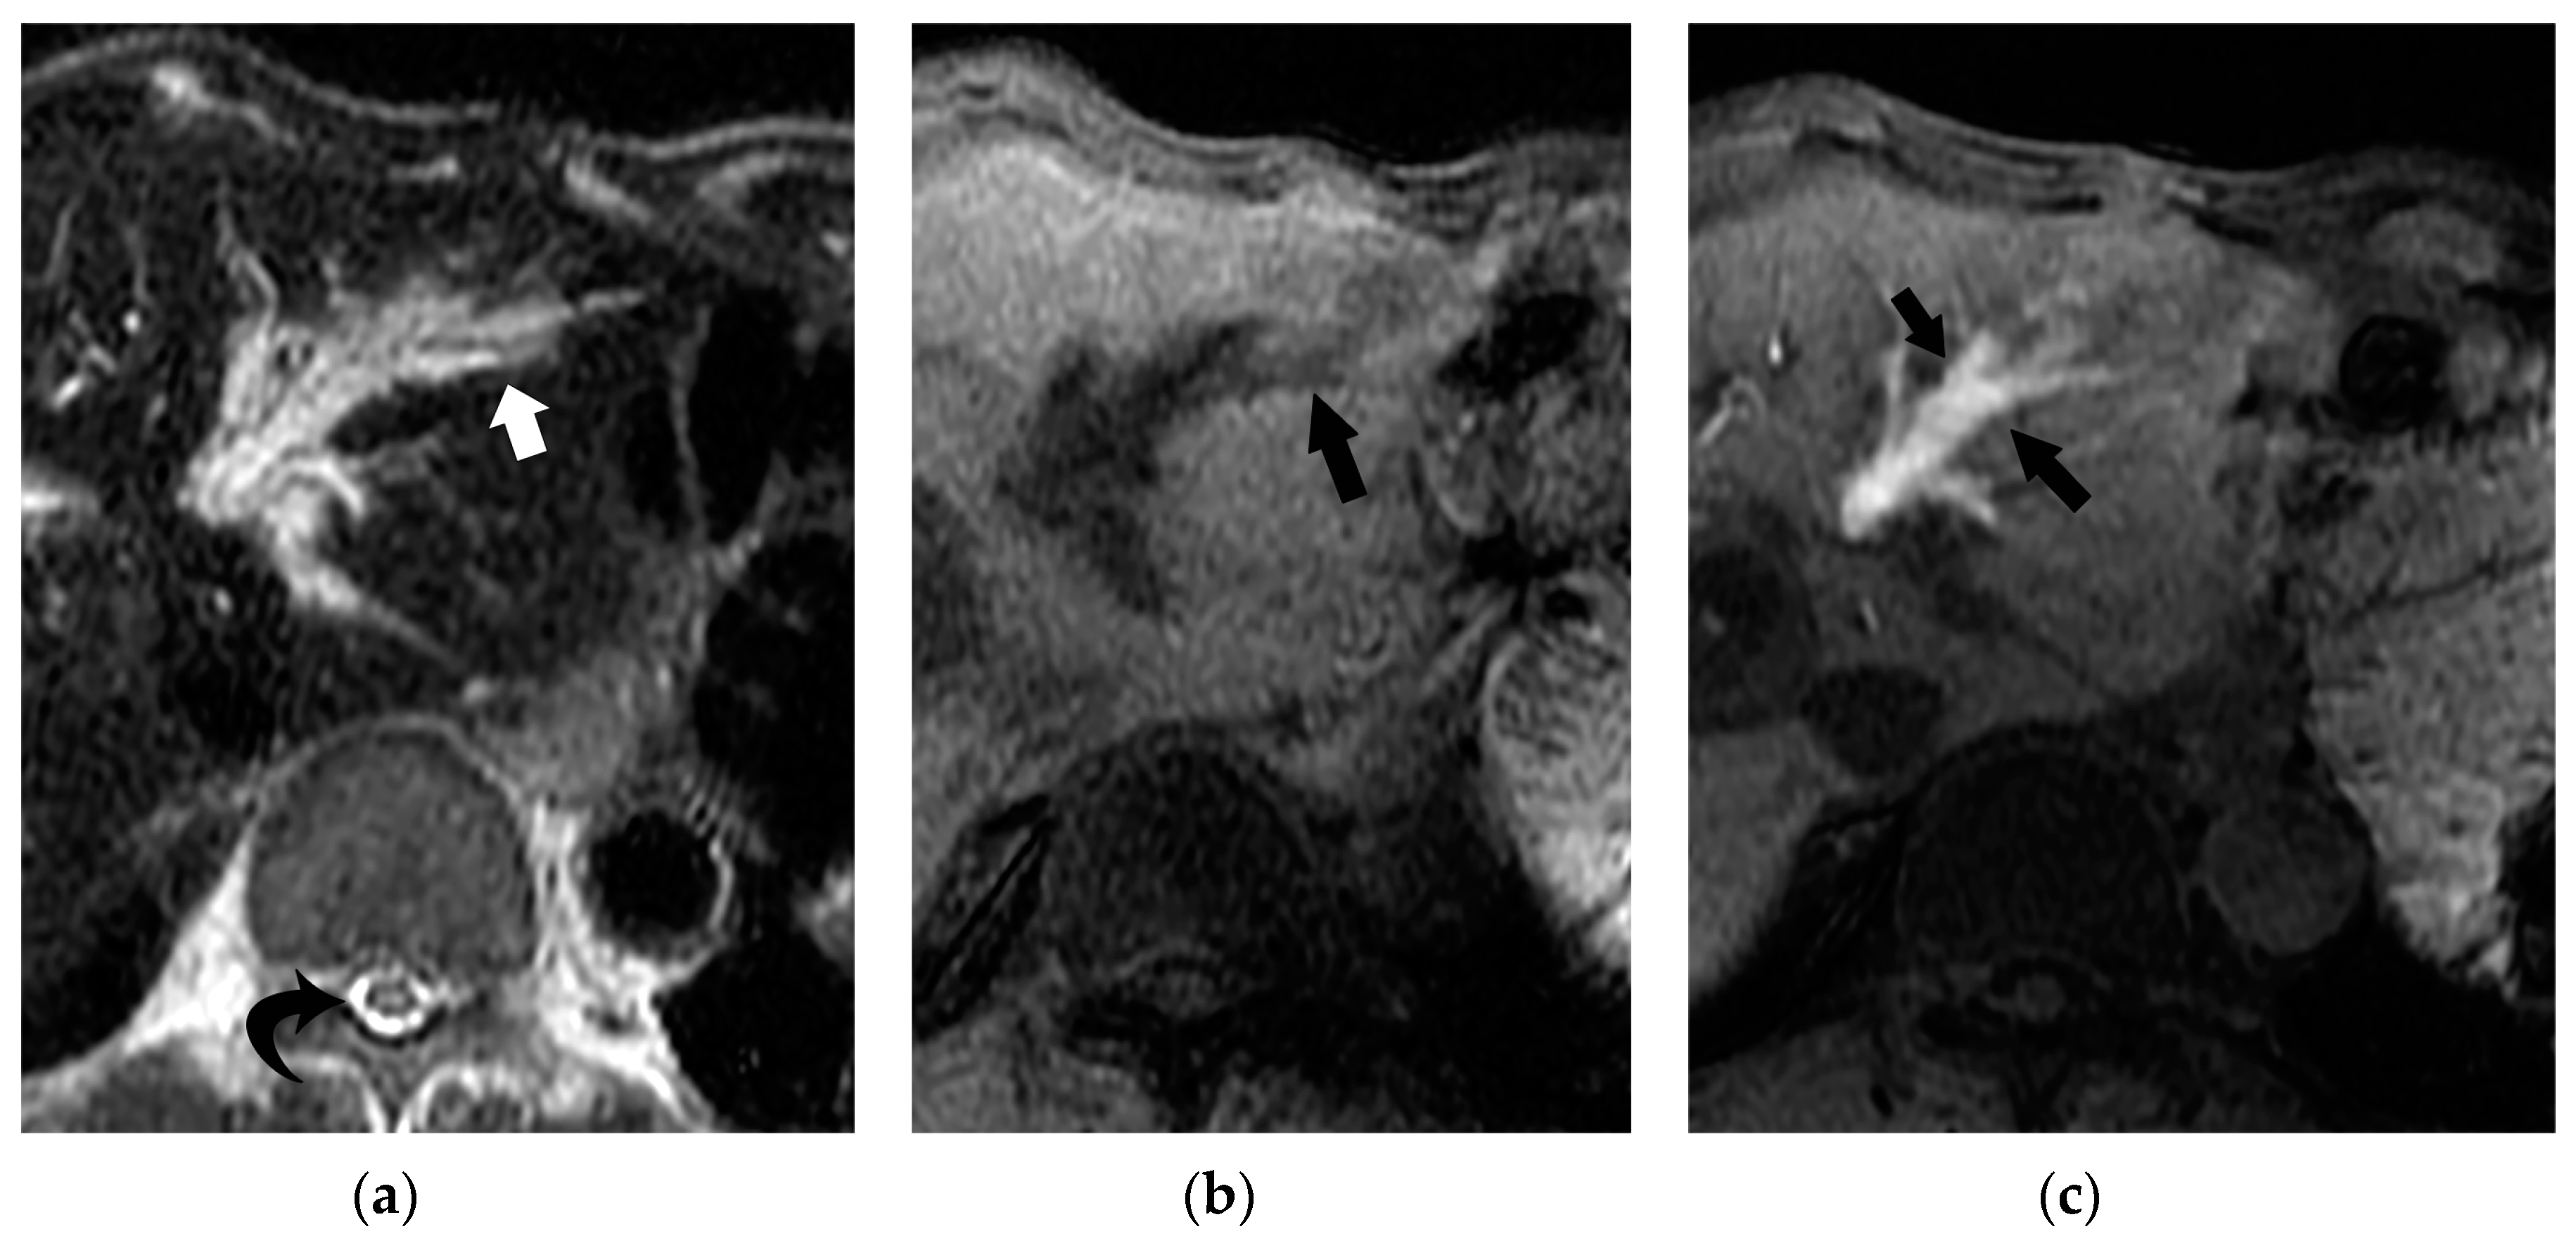

• T2-weighted MR findings of bile duct necrosis

On T2-weighted MR images, BDN does not show marked high intensity, but slightly high intensity, which represents portal tract damage caused by imbibed bile salt, rather than a fluid-filled dilated bile duct (Figure 13). On MR cholangiopancreatography (MRCP), a necrotic portion of BDN shows variable signal intensities depending on the ratio of water to necrotic tissue (with/without hemorrhage) contents on heavy-T2 weighted images, which reflects the absence of intrahepatic bile duct dilation at the BDN site (Figure 14). Recognizing the difference between the T2-weighted MR images and CT findings provides confidence in making a diagnosis of BDN and not intrahepatic bile duct dilatation.

Figure 13. Comparison between CT and T2-weighted MRI findings of BDN. (a) On contrast-enhanced CT, a hypodense irregular tubular structure (*) is observed in the left lateral segment of the liver. Although this tube-like structure looks like irregularly dilated intrahepatic bile ducts, it is BDN. Biloma formation (arrow) is observed at the peripheral portion of the lateral segment which is connected to BDN. On the hepatic hilum, slightly dilated right and left hepatic ducts are observed (arrowheads). (b) On T2-weighted MRI, BDN (*) and biloma (arrow) on the left lateral lobe of the liver do not show marked hyperintensity like the hepatic ducts (arrowheads), but instead show slight hyperintensity. This finding suggests that BDN and biloma are not pure fluid-filled spaces, but “necrotic tissue”. (Figure 13a is same figure as Figure 9. It is presented for comparison with Figure 13b).

Cancers 12 02596 g013